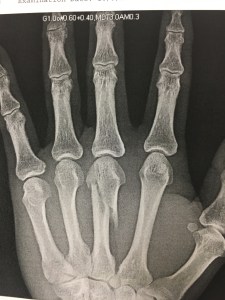

My left hand’s middle metacarpal bone was broken playing basketball at CSL on 10/1/17 in Bellevue. I swiped a pass a guy hand monster grip that held onto for dear life but I knocked it out of bounds. That was in the first few minutes of the game and I played the rest of it thinking I only sprained my finger. But I knew something was wrong after the game cuz it didn’t feel like a sprain anymore. I didn’t know it was broken, though! Geezmeneez. First broken bone and first operation in my life. I played volleyball after the operation to finish out that season as my team there, WePlay, needed players. But rehab is helping greatly and I’ll be back 100% by February 2018.